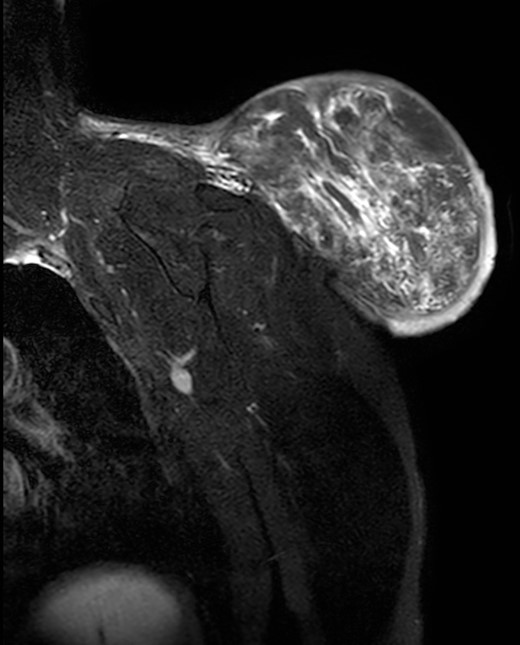

During the follow-up, a magnetic resonance (Figs 3 and 4) was performed describing a soft tissue lesion highly suggestive for liposarcoma as a first possibility diagnosis, with an addition image suggesting metastatic axillary lymph node. After the imaging results, biopsies were taken and analysed by the pathologist with a final diagnosis of PL.

Magnetic resonance imaging T2 with contrast: giant excrescent lesion of 19 × 18 × 14.4 cm of diameter located in the subcutaneous tissue of the posterior aspect of the scapula divided by multiple septums; axillary lymph node of ~0.9 cm; images compatible with liposarcoma with a metastatic axillary lymph node.

Magnetic resonance imaging T1: polylobulated lesion with multiple septa separating different areas of fat tissue.